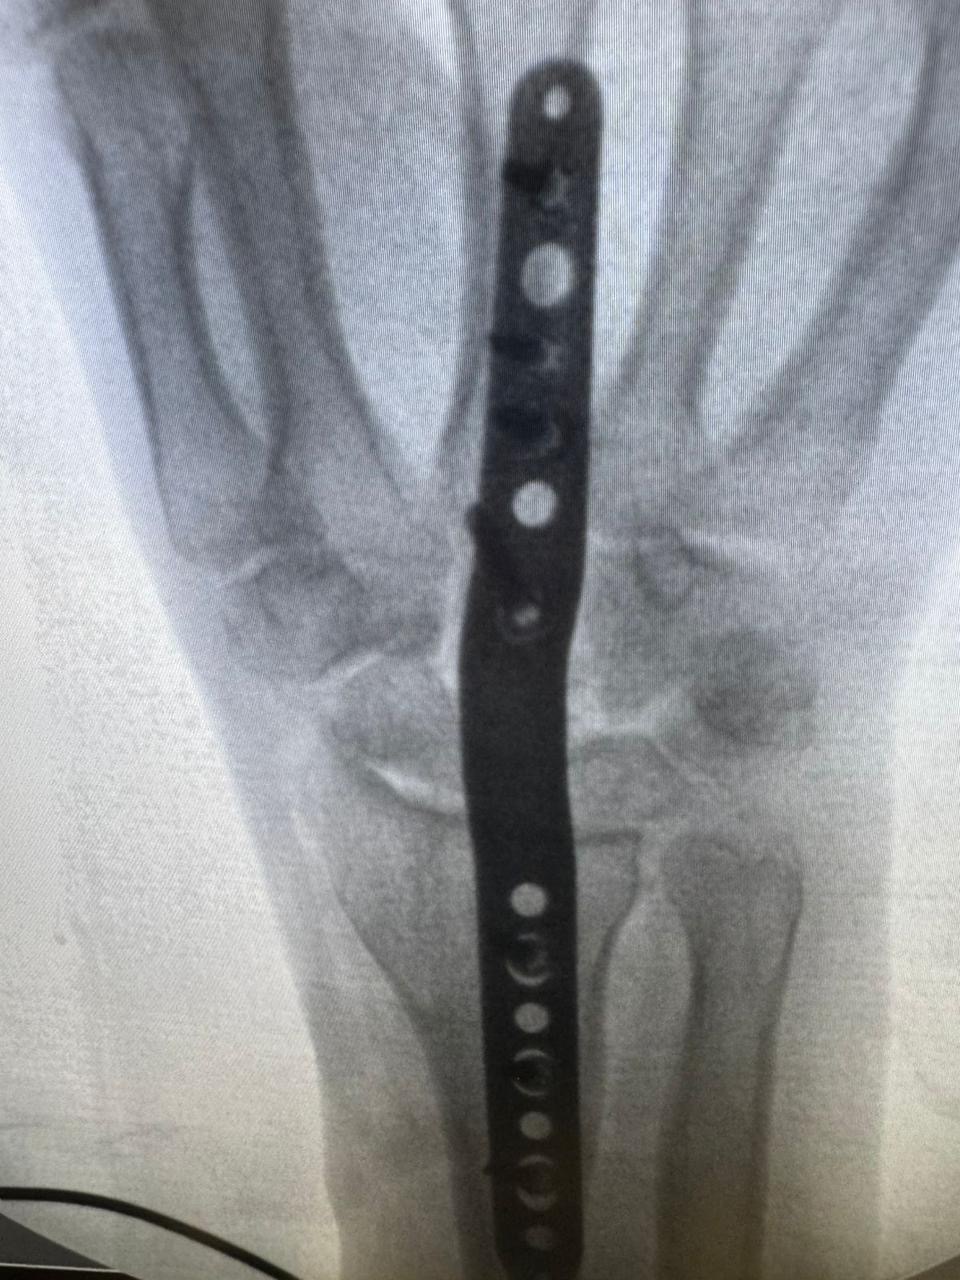

وقال فارس:“تم تحويلي لطبيب في القاهرة، وفضلت مستني من شهر 12 لسنة 2023 لحد شهر 2 لسنة 2024 عشان العملية تتعمل، وبعد أول غيار فوجئت إن العملية اتعملت جراحة مفتوحة مش منظار، رغم إن التقارير كانت بتوصي بمنظار.”

وأضاف:“لما سألت الطبيب عن سبب إجراء جراحة بدل المنظار، قالي إن الجراحة أفضل وإن إيدي هترجع أحسن من الأول، لكن بعد انتهاء فترة الجبس وخضوعي لجلسات علاج طبيعي، اكتشفت إن حالتي لم تتحسن، وإن إيدي محتاجة تدخل جراحي تاني.”

“خطأ طبي ضيّع مستقبلي.. وآخر عملية كانت تثبيت مفصل”

وأكد اللاعب أن ما حدث له هو نتيجة خطأ طبي، قائلًا:“الدكتور استسهل إجراء الجراحة بدل المنظار، وده تسبب في مضاعفات خلتني أرجع أعمل عمليات تانية، آخر عملية كانت في شهر أكتوبر اللي فات، وتم فيها تثبيت مفصل، ومع عمليات أخرى، للأسف إيدي مش هترجع زي الأول بسبب الخطأ الطبي.”